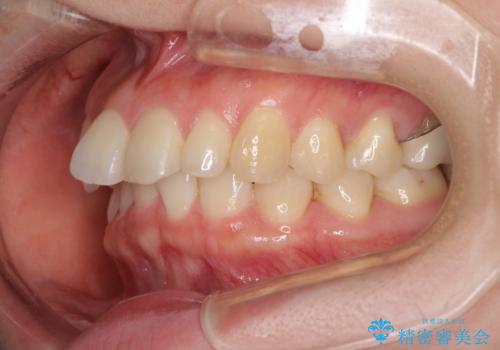

先天欠損のある歯列 インビザライン矯正

- 上顎前歯の突出感を気にして来院された患者様です。

下顎前歯2本が先天欠損しており、上顎歯列に対して、下顎歯列がアンバランスに小さい状況でした。

左右上顎側切歯2本が矮小歯であるため、上顎の抜歯ではなく、IPR(歯と歯の間を削る)と歯列全体の後方移動によってバランスを整えることとしました。

目立ちにくい装置を希望されたため、インビザラインにて治療を行うこととしました。

歯列のバランスが悪く、インビザライン矯正特有の奥歯の噛みにくさがなかなか改善されず、治療期間が長期化してしまいました。